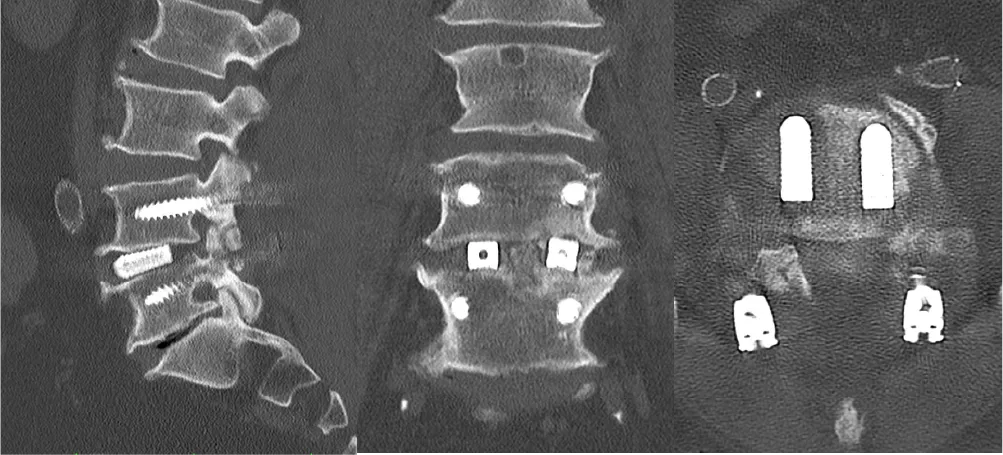

脊椎破裂骨折

治療法:骨折した椎骨の上下の椎骨に経皮的にスクリューを挿入し、変形を矯正します。さらに骨折した椎骨に人工骨を充填し、骨折部を安定させます。手術翌日から歩行が可能となり、入院期間は1〜2週間程度です。骨折部が治癒した後にスクリューなどは抜去します。

胸椎破裂骨折に対する経皮的内固定術

• 骨折部は人工骨を充填して整復